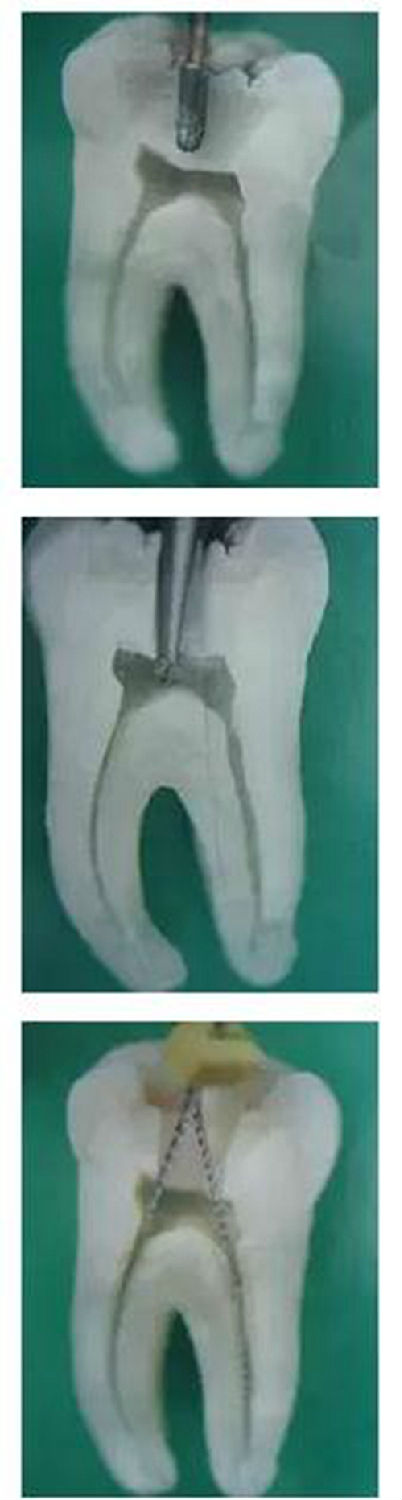

1,開髓:洞型是否制備的符合要求,髓室頂是否揭得剛剛好,沒有破壞洞壁及洞底結(jié)構(gòu)。。。

圖1,裂鉆鉆到近髓 2,球鉆穿髓 3,小號(hào)銼探查根管口

圖4,球鉆揭髓頂 5,修整洞型 6,完成開髓